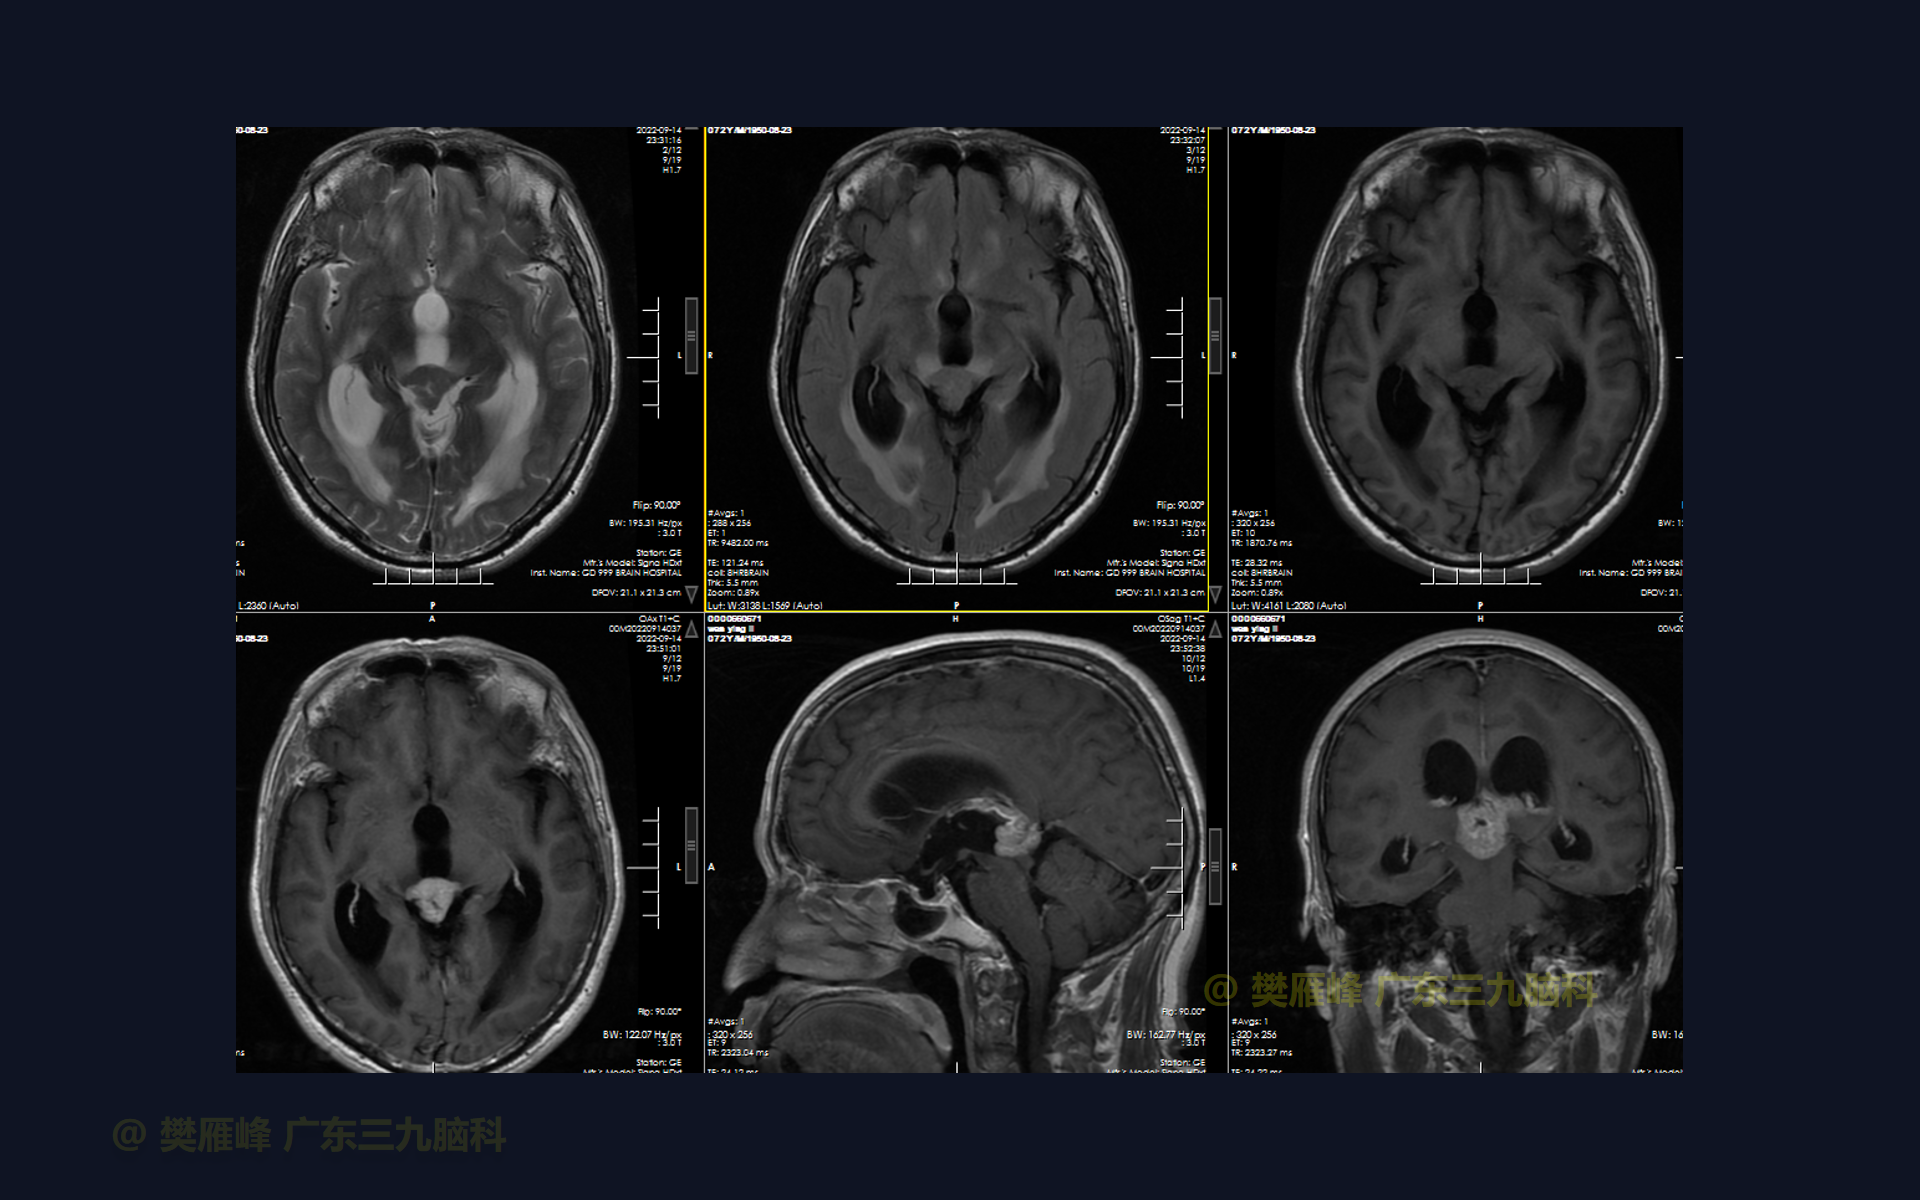

在这个二维手术视频中,展示了2例神经内镜下三脑室底造瘘+活检治疗三脑室后部肿瘤的方法。患者均为三脑室后部病变导致的梗阻性脑积水,病理结果1例为生殖细胞瘤,1例为淋巴瘤,在经过术后的放化疗病情均得到控制,生活质量满意。我们展示了安全的病变活检和第三脑室造瘘的技术要点,以最大限度减少术后继发脑积水和早期并发症。